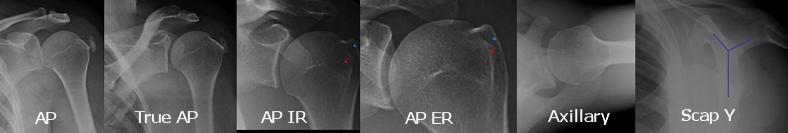

어깨나 쇄골이 부러진 경우 기본적으로 X-ray 를 통해 골절의 상태난 전위정도를 파악하게 됩니다.

trauma 시에 가장 기본적인 검사는 AP와 axillary lateral view 입니다.

1. shoulder AP

glenohumeral joint space, DJD

2. True shoulder AP

Glenohumeral joint space, DJD, and proximal migration of humerus

3. axillary lateral view

상완골의 탈구/아탈구 를 확인해 볼 수 있습니다.

4. Scapular Y lateral view

acromion이 보이긴 보입니다.